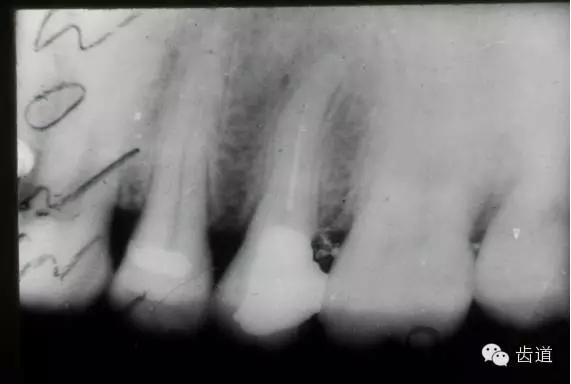

左下7根充后下唇麻木

左下5根管預(yù)備后下唇麻木

1.作根管治療前拍X線片,下頜牙齒應(yīng)特別注意與下頜管的關(guān)系。

2.準(zhǔn)確測(cè)量根管工作長(zhǎng)度,各種操作均在工作長(zhǎng)度范圍內(nèi)進(jìn)行。根管封藥不可過(guò)飽和,防止藥液溢出根尖孔。